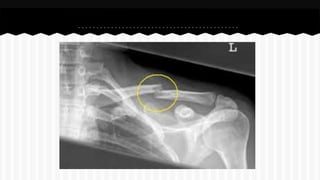

RESPONDA O NOME DO OSSO EM QUE

SE ENCONTRA A (S) FRATURA (A).